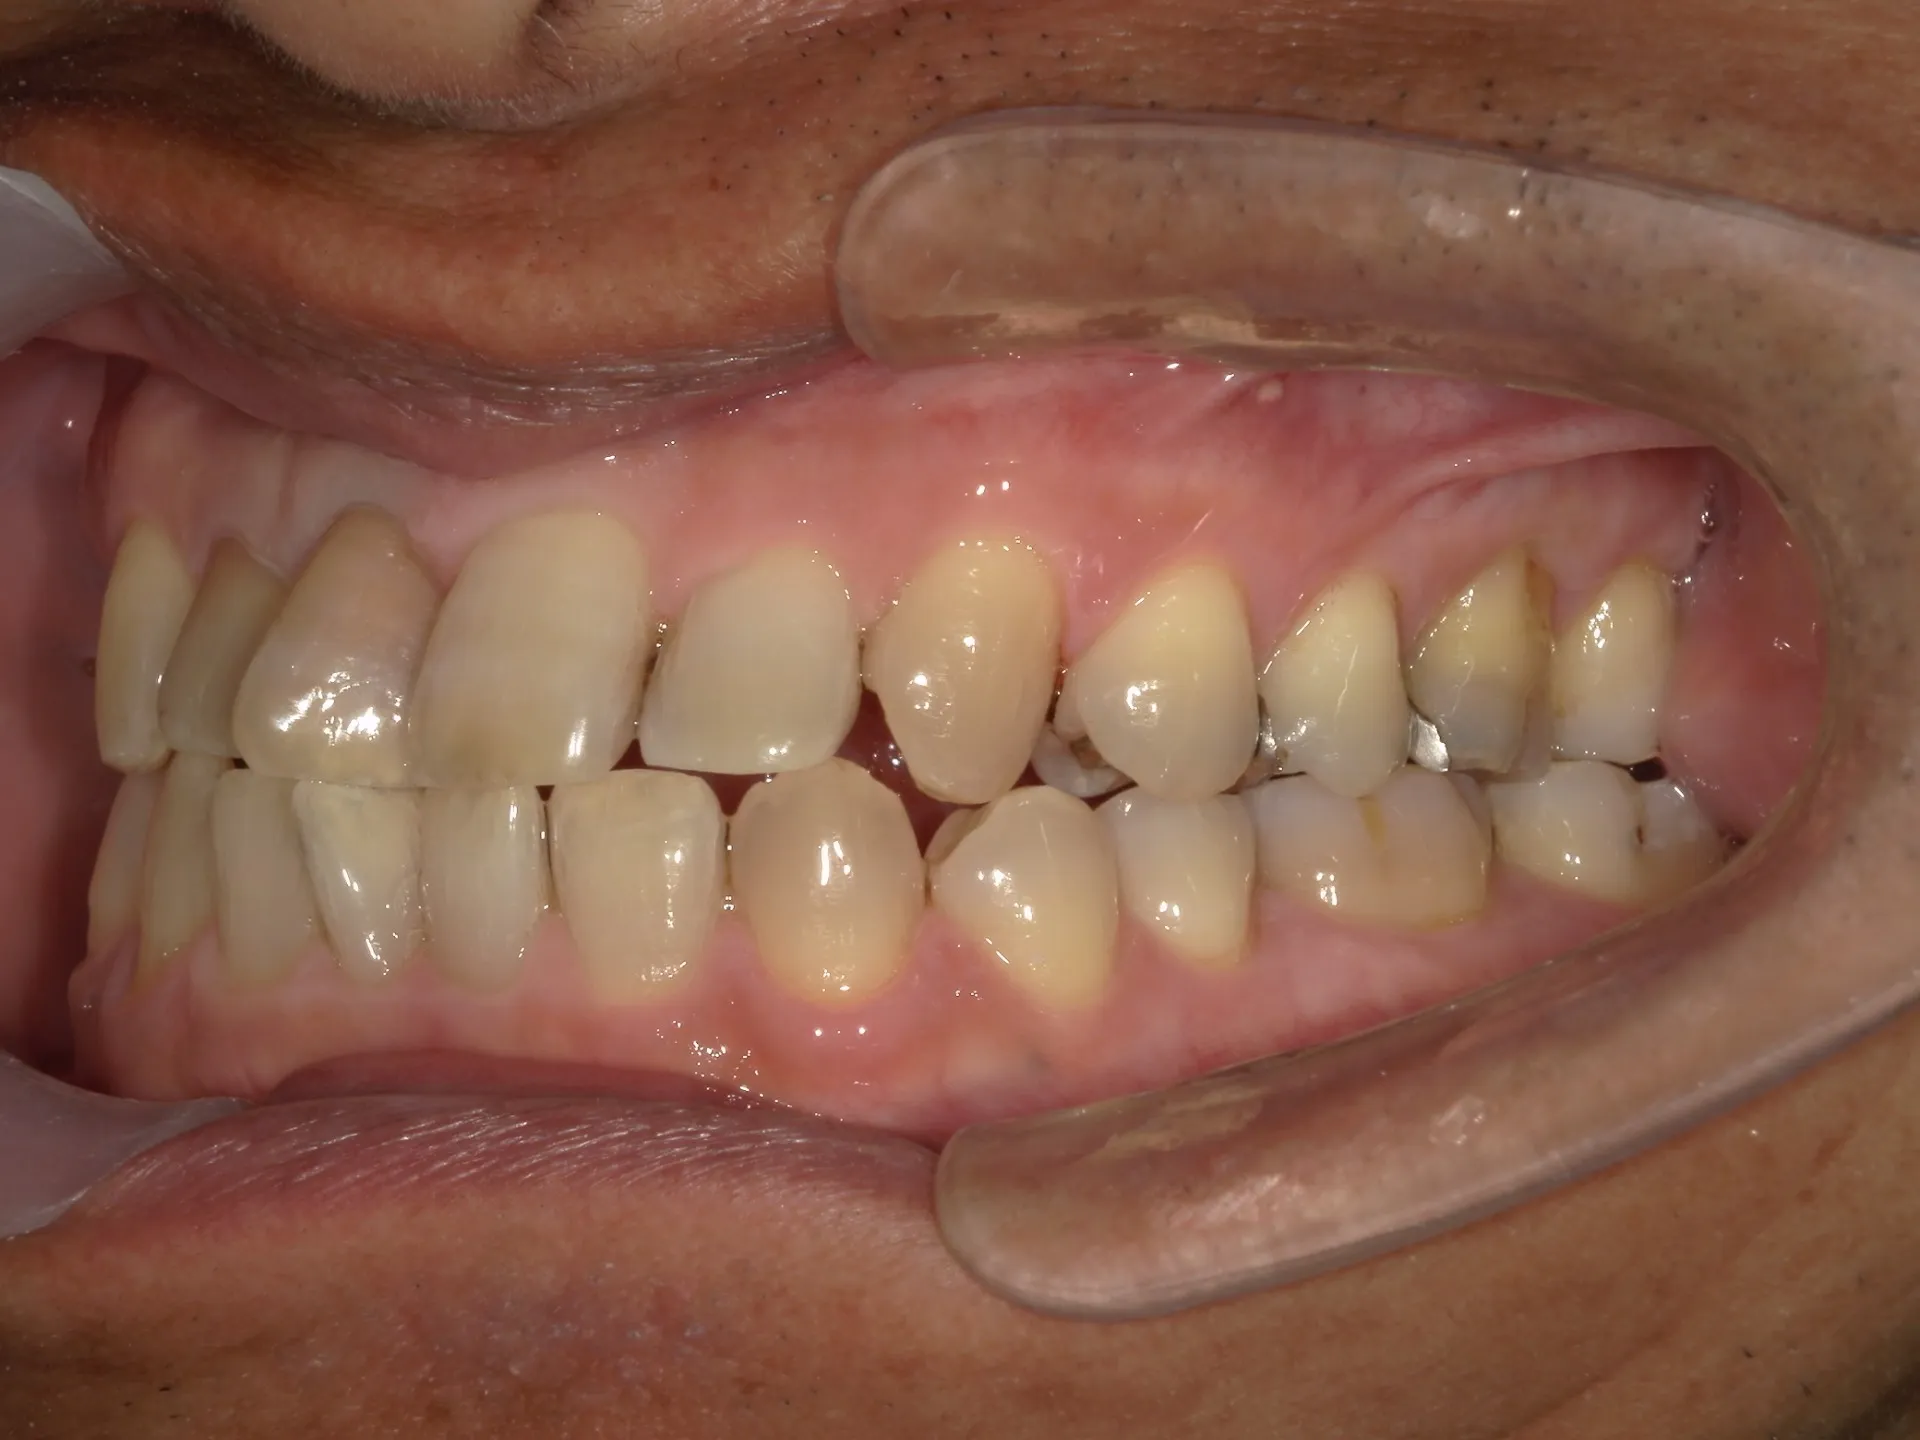

① 保険の歯の掃除(スケーリング・ルートプレーニングなど)

目的:歯周病(歯肉炎・歯周炎)の治療、進行予防

対象:歯石やプラークの除去

範囲:医療行為として認められた範囲のみ(歯石やプラークがついていないと保険は算定できません)

内容:歯周ポケット検査を行い、その後超音波スケーラーや手用スケーラーで歯肉縁上・縁下の歯石を取る